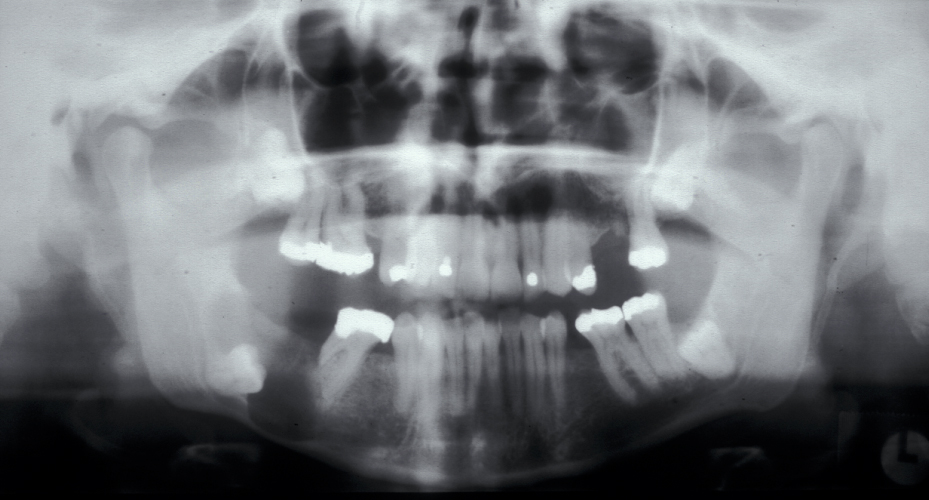

Assessment of the tooth is both clinical and radiographic. If somebody presents in pain, it is important to establish that this is coming from the third molar and not elsewhere. Pain is often vague, poorly localised and may be referred from another tooth, or as part of facial arthromyalgia (condition affecting the jaw joint). A dental panoramic radiograph is ideal as it helps to assess all the teeth at once. The health of the adjacent molars may influence the decision whether to remove the third molar or not. Large crowns or old restorations are all at risk of dislodgement during surgery. It is also worth considering whether alternative treatment options are available. For instance, pericoronitis due to an over-erupted upper third molar may be dealt with by extracting that tooth only, with or without operculectomy. In the presence of other teeth of poor prognosis, will it be better in the long term to save the third molar which may be used as a denture or bridge abutment in the future?

These points help to determine whether the tooth can be simply elevated or will need a surgical approach. A series of radiographs depicted in Figure 4 to Figure 8 illustrate these points further.